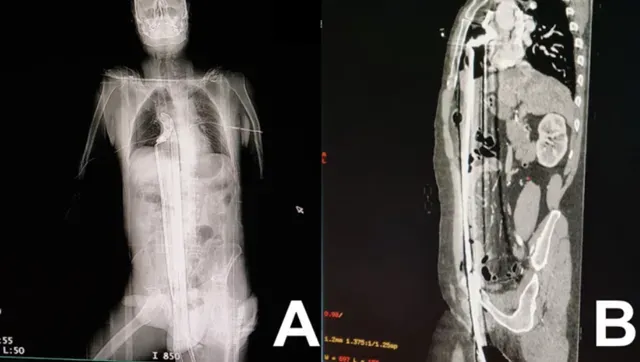

57歲工人從鷹架墜落被鐵棒刺穿全身!奇蹟生還出院 驚悚貫穿照曝光